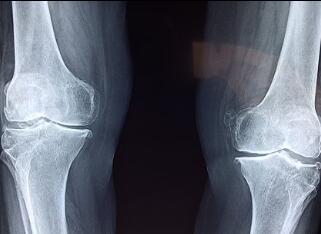

نظرت الوالدة إلى هدوء لونغ لونغ واستمرت قائلة: "كل شيء يكون له جانب ضار، وسيكون له جانب مفيد للآخرين. الجيد أو السيئ ليس سمة من سمات الشيء نفسه. ويعتمد على من يستخدمه وأين يستخدمه. ومثل المتفجرات، يمكن أن تؤذي الناس، وكما يمكن فتح الجبال لانشاء الطرق. والأشعة السينية هي نفسها، وبعض التشخيصات الطبية، وخاصة جراحة العظام، تتطلب الأشعة السينية للمساعدة في تحديد العظام المكسور ومكان حدوث الكسر ".